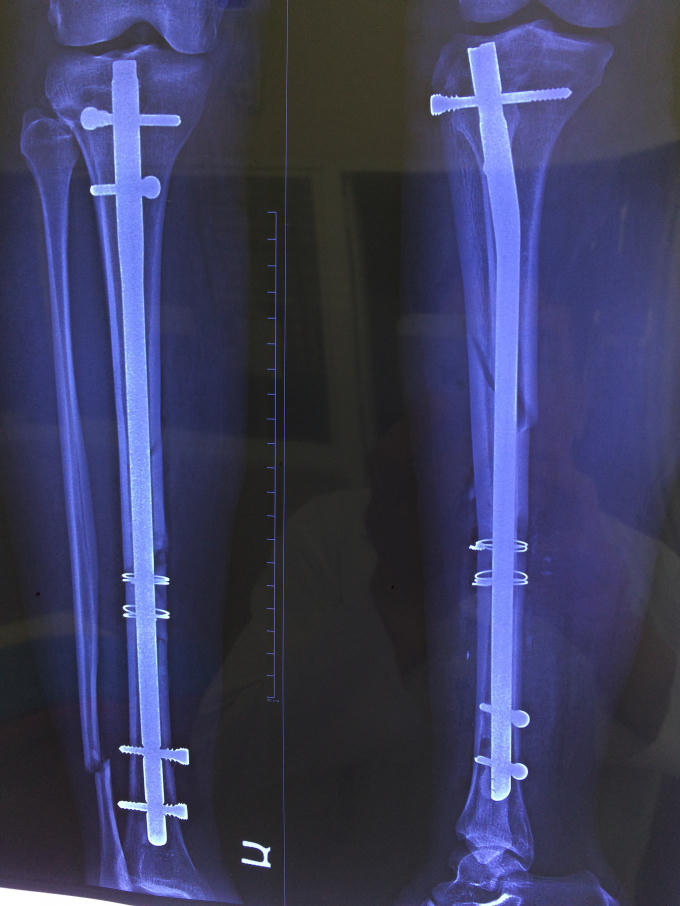

Bác sĩ Phạm Thanh Vũ, Phụ trách khoa Ngoại Chấn thương, Bệnh viện Quận 11 đã tiếp nhận ca này. Sau khi phối hợp với các bác sĩ khoa Tim mạch chuyển hóa, khoa Chẩn đoán hình ảnh, khoa Gây mê hồi sức... và hội chẩn toàn bệnh viện; các bác sĩ ghi nhận, bệnh nhân bị gãy xương cẳng chân bên phải (đoạn ống quyển) thành 2 đoạn phức tạp.

Cuối cùng, các bác sĩ quyết định không gây mê toàn thân vì nguy hiểm mà chỉ thực hiện phẫu thuật kết hợp xương bằng phương pháp gây tê mỗi vùng cẳng chân.

Ca mổ kéo dài một giờ, bệnh nhân được kết hợp xương bằng đinh nội tủy có chốt. Sau mổ, bệnh nhân tỉnh táo, cử động chân được. Dự kiến chị Lê Thị Ngọc D. sẽ tập đi lại và xuất viện sau 1 tuần.